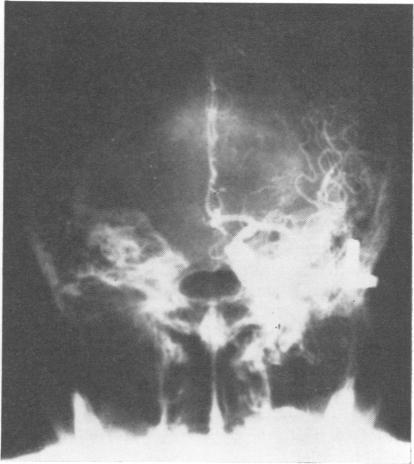

A 58 year old woman presenting with abdominal distress and a neuropsychiatric disturbance with evidence of focal neurological deficit is described. A diagnosis of pancreatic encephalopathy was made, and the patient was treated accordingly with pancreatic anti-enzymes. A survey of the literature is presented.

本文描述了一名58岁女性,她出现腹部不适和神经精神障碍,并伴有局灶性神经功能缺损的证据。诊断为胰腺性脑病,患者接受了相应的胰酶抑制剂治疗。同时还对相关文献进行了综述。